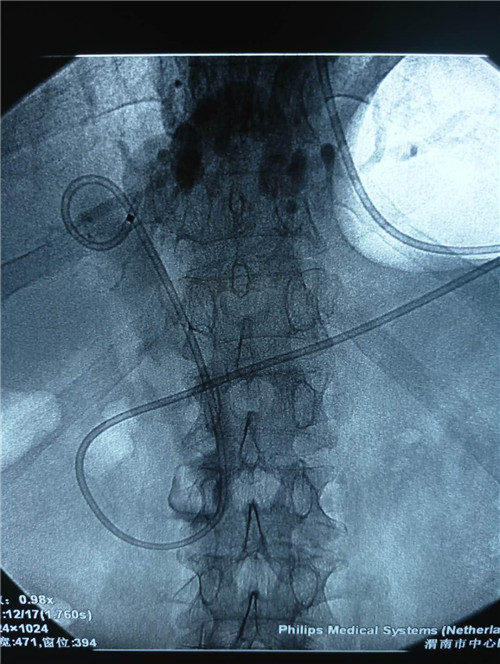

曹鹏医生进十二指肠镜后看到肿大的乳头,利用切开刀+导丝超选进入胆管,行十二指肠乳头切开,随即大量脓性胆汁流出,并迅速留置鼻胆管。功夫不负有心人,终于,在主管护师许晓庆、护士王欣的配合下,又成功挽救了一名病患的生命,同时也彰显了市中心医院消化内镜中心医护人员极高的专业素养和娴熟的业务能力。